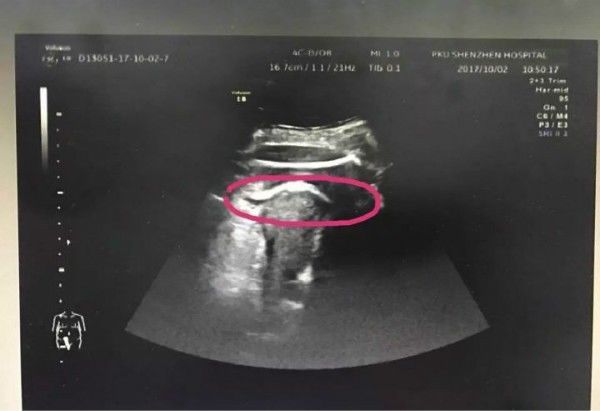

医生初步怀疑患者子宫破裂,当即安排做了B超。检查发现,胎儿的一条腿“踢破”了子宫,进入了腹腔,大腿根正卡在子宫壁上!

▲红色圆圈处是胎儿的腿,已经伸到子宫壁外

医生追问患者病史,原来张女士2016年做过子宫肌瘤剔除术,术后半年就怀孕了。不到2分钟B超检查,仅凭有限病史,医生快速作出诊断:高度怀疑为疤痕子宫破裂